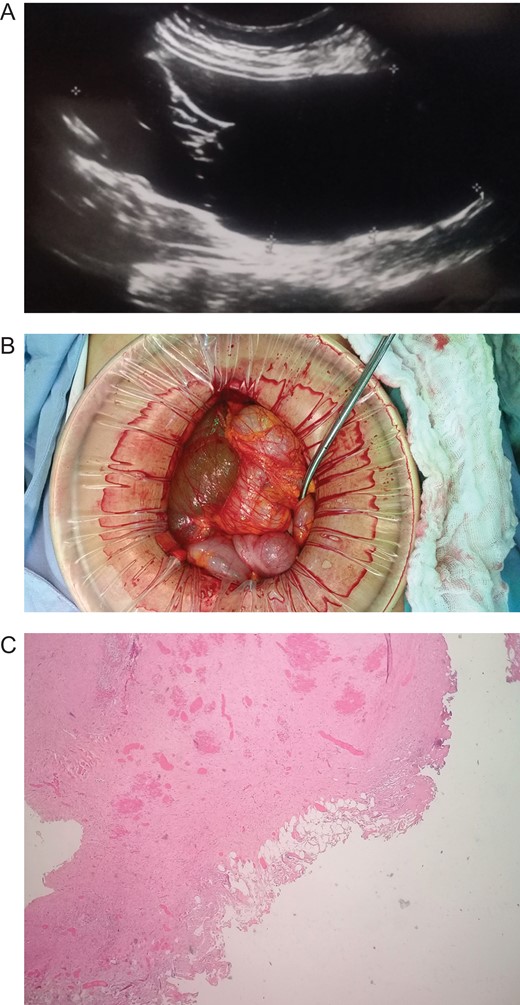

Patient is a 45-year-old female patient, with past medical history of gastritis. Six months before she sought medical attention, she was complaining of mild upper abdominal pain, however, due to her previous condition she was medicated with proton pump inhibitors assuming that the pain was due to her gastritis. In the last 3 months, she noticed a mass in her upper abdomen and the pain became more severe and started to affect her daily activities, thus she presented to a routine physical exam. No weight loss or other constitutional symptoms were noticed. Also no history of malignancy in her family was mentioned. On clinical examination, a 12 × 15 cm2 mass was discovered on her upper abdomen, mild pain was found on palpation but no tenderness was present. An abdominal ultrasonography revealed a 15 × 15 cm2 septate thin-walled giant cystic mass, it was anechoic and had a volume of ~735 ml. The cyst occupied most of the hepatorenal space and it was in intimate contact with the liver, right kidney and pancreas (Fig. 1A). Due to the size of the mass, CT was requested, it revealed well-defined 19.7 × 15 × 10 cm3 giant cyst, the cyst was located within the small bowel mesentery and it was in intimate contact with the liver, gallbladder, pancreas and right kidney (Fig. 2A). Nevertheless, the tomography could not rule out that the mass had some sort of communication with the bile duct or the pancreas. This is why a magnetic resonance cholangiopancreatography found that the cyst was attached but had no communication with the bile duct or the pancreas (Fig. 3A). CBC and blood work was normal.

(A) CT revealing a well-defined 19.7 × 15 × 10 cm3 giant cyst. (B) Giant cyst surrounded by the bowel. (C) Pathology, cyst wall covered by adipose tissue. (Hematoxylin and eosin staining 40×.)

Due to the size of the cyst and clinical condition surgery was planned. At laparotomy, a 19 × 15 × 10 cm3 mesenteric cyst was discovered (Fig. 1B), the cyst was near the root of the small bowel mesentery but did not compromise its main vessels, it had a yellowish appearance (Fig. 2B), and clear fluid was found within the cyst. Multiple adhesion were identified between the cyst wall and the transverse colon, liver, third portion of the duodenum and gallbladder. With these findings surgery was straightforward, complete resection of the cystic mass was performed, however, the cyst wall was completely attached to the body of the gallbladder and could not be resected without compromising it (Fig. 3B), so a cholecystectomy was performed as well. After this, the remainder of the procedure continued without any complication.

Pathology reported a giant primary mesenteric cyst, it was lined with a single layer of cuboidal epithelial cells and partially covered by adipose tissue and prominent vasculature, it had a yellowish wall and its thickness varied between 0.1 and 0.3 cm (Fig. 1C). Its interior had a white trabecular internal surface with brown patches it did not have any communication with other organs, and no areas of malignancy were found (Fig. 2C).